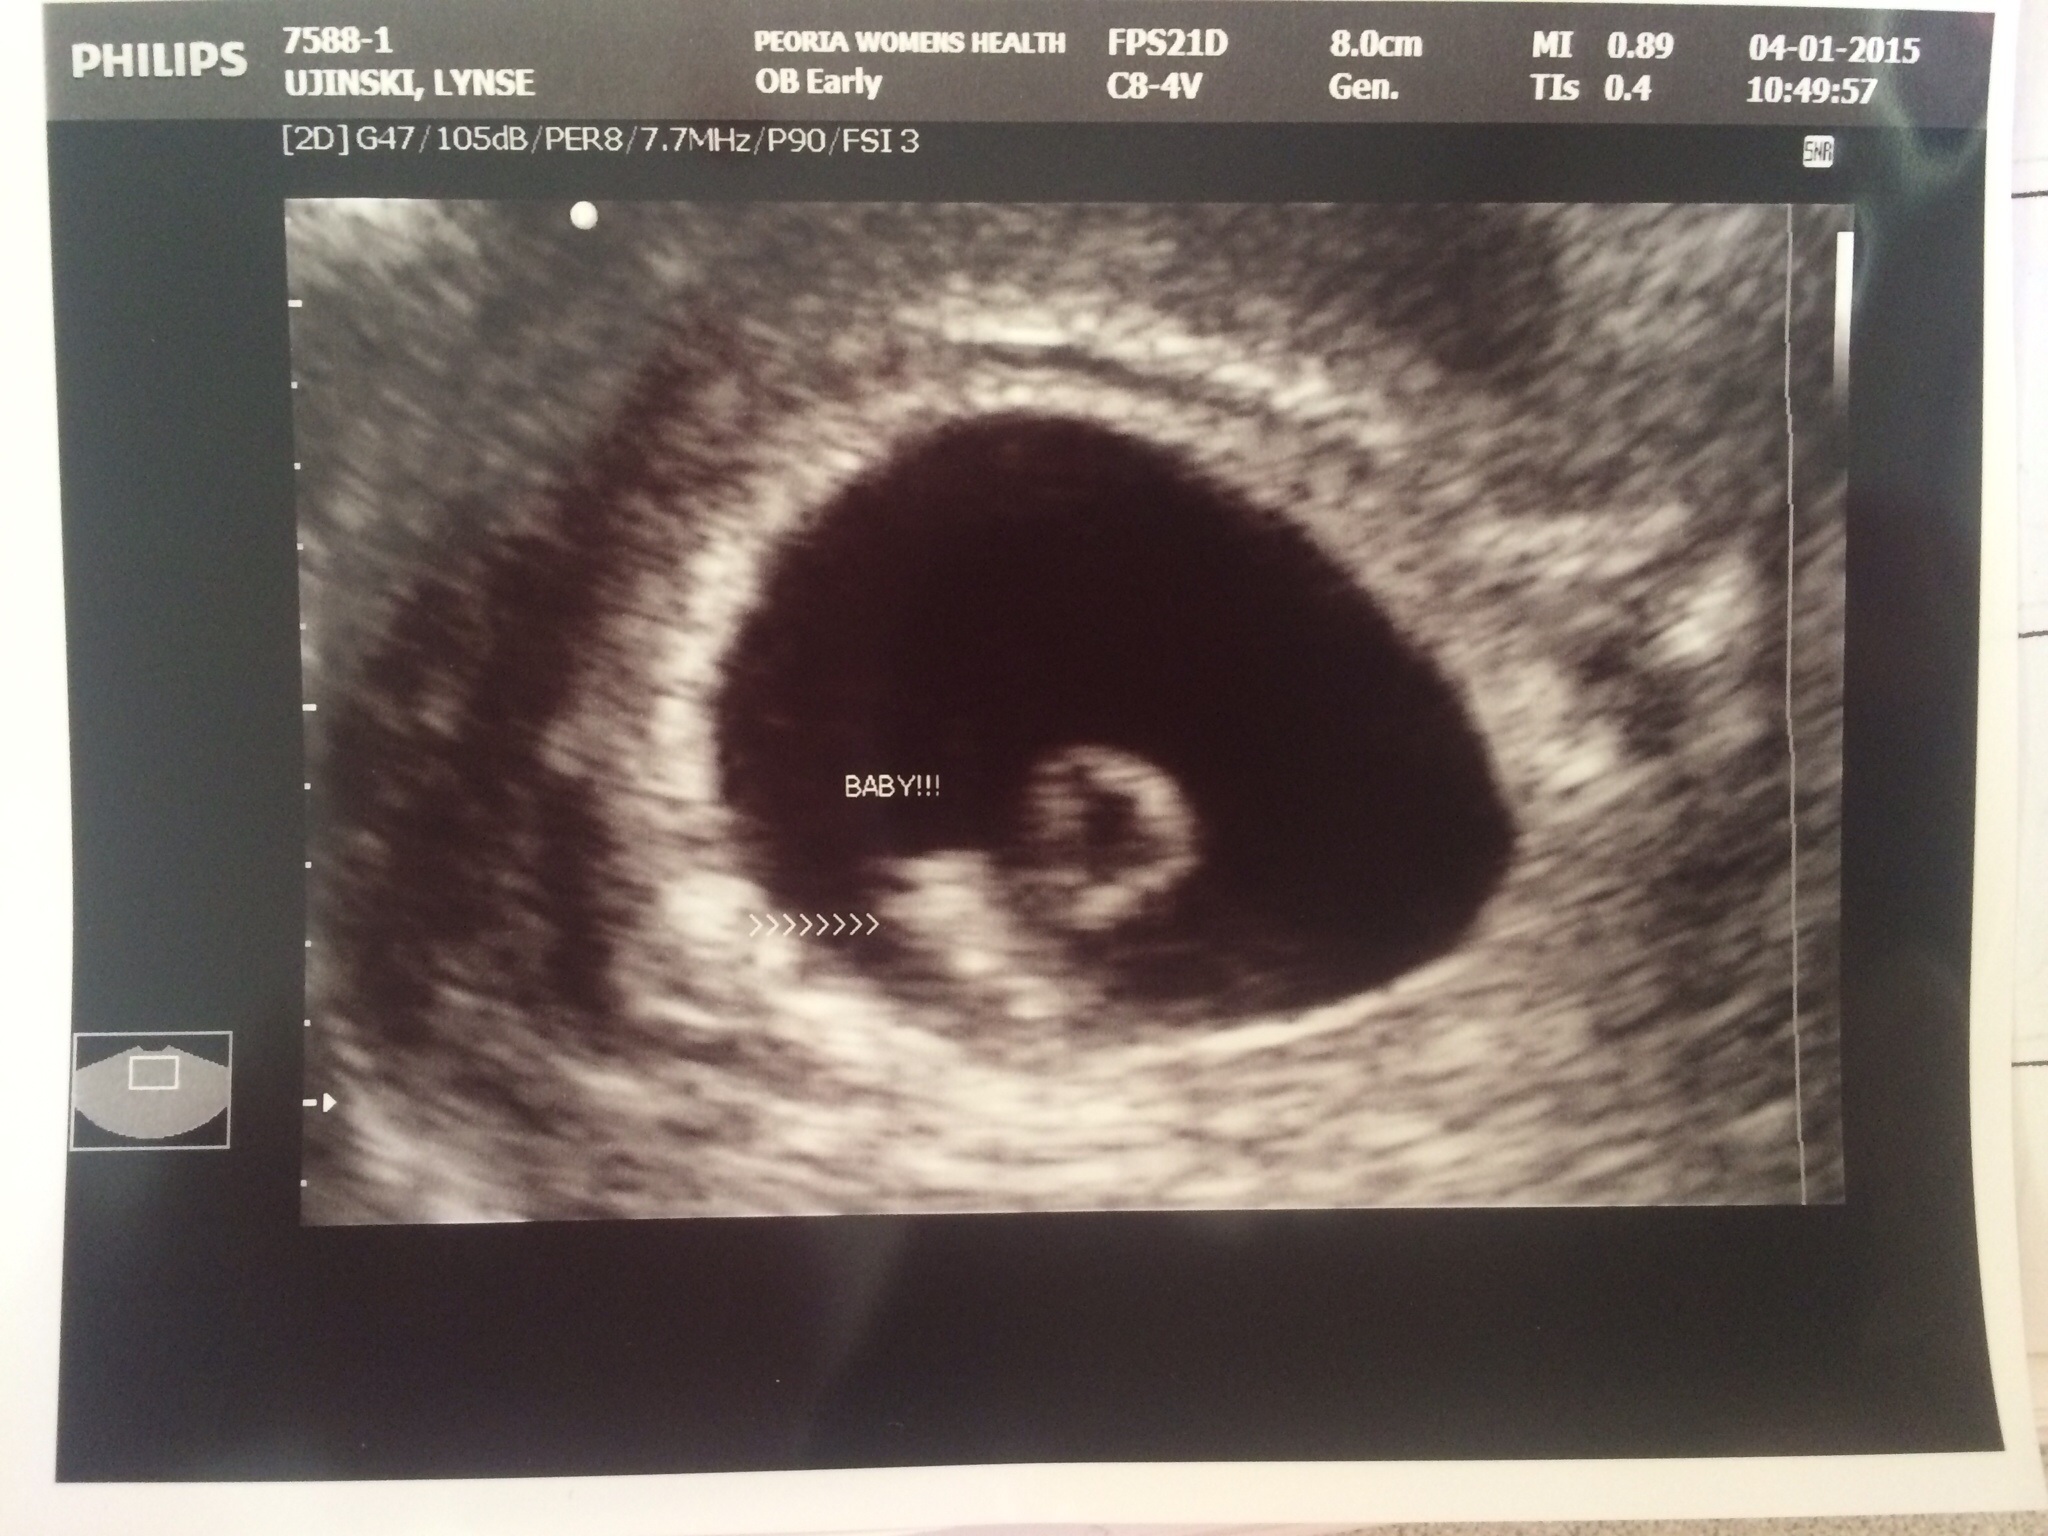

this was 7w1d I am 8w now.  I ran around waving it and telling people, "look!  Look what's in my uterus because I had sex!"  Toby said I was weird and needed to tone it down to "I am pregnant, would you like to see the u/s?" lmao  I word things oddly.